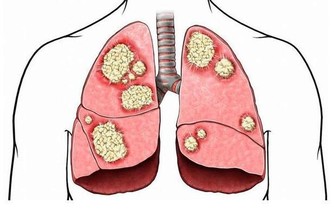

2.腦變性疾病:

腦變性疾病引起的癡呆有許多種,最為多見的是阿爾茨海默病性癡呆,在老年前期發病的又叫做早老性癡呆。其發病緩慢,為逐漸進展的進行性癡呆。除此之外,還有皮克病、廷頓舞蹈病性癡呆、進行性核上性麻痺、帕金森病性癡呆等等。後面的這些癡呆都比較少見。